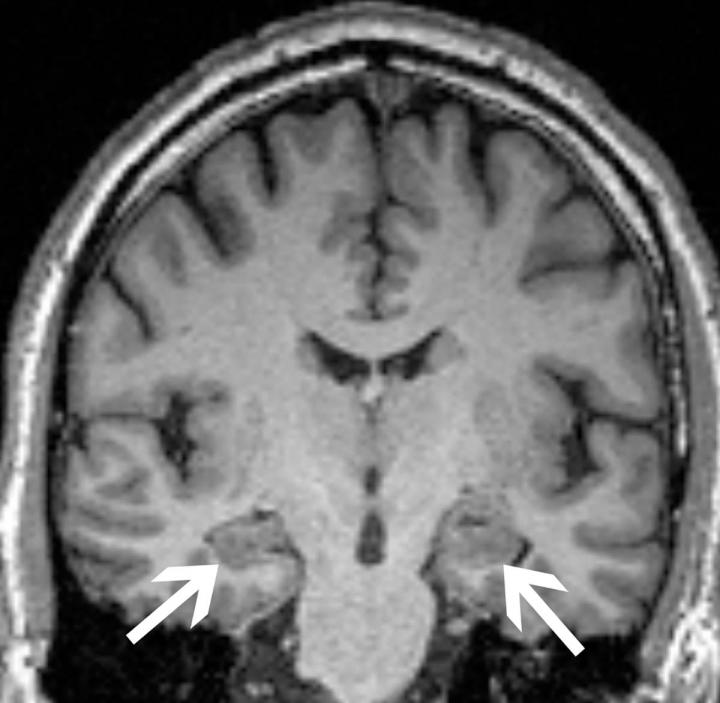

The researchers obtained brain MRIs to determine the baseline volumes of the hippocampus and the entorhinal cortex, two areas important to forming memories. They also tested for the presence of the ApoE4 allele, the most prevalent genetic risk factor for Alzheimer's disease. Anxiety was measured with established clinical surveys.

As expected, patients who progressed to Alzheimer's disease had significantly lower volumes in the hippocampus and the entorhinal cortex and greater frequency of the ApoE4 allele. Most notably though, the researchers found that anxiety was independently associated with cognitive decline.